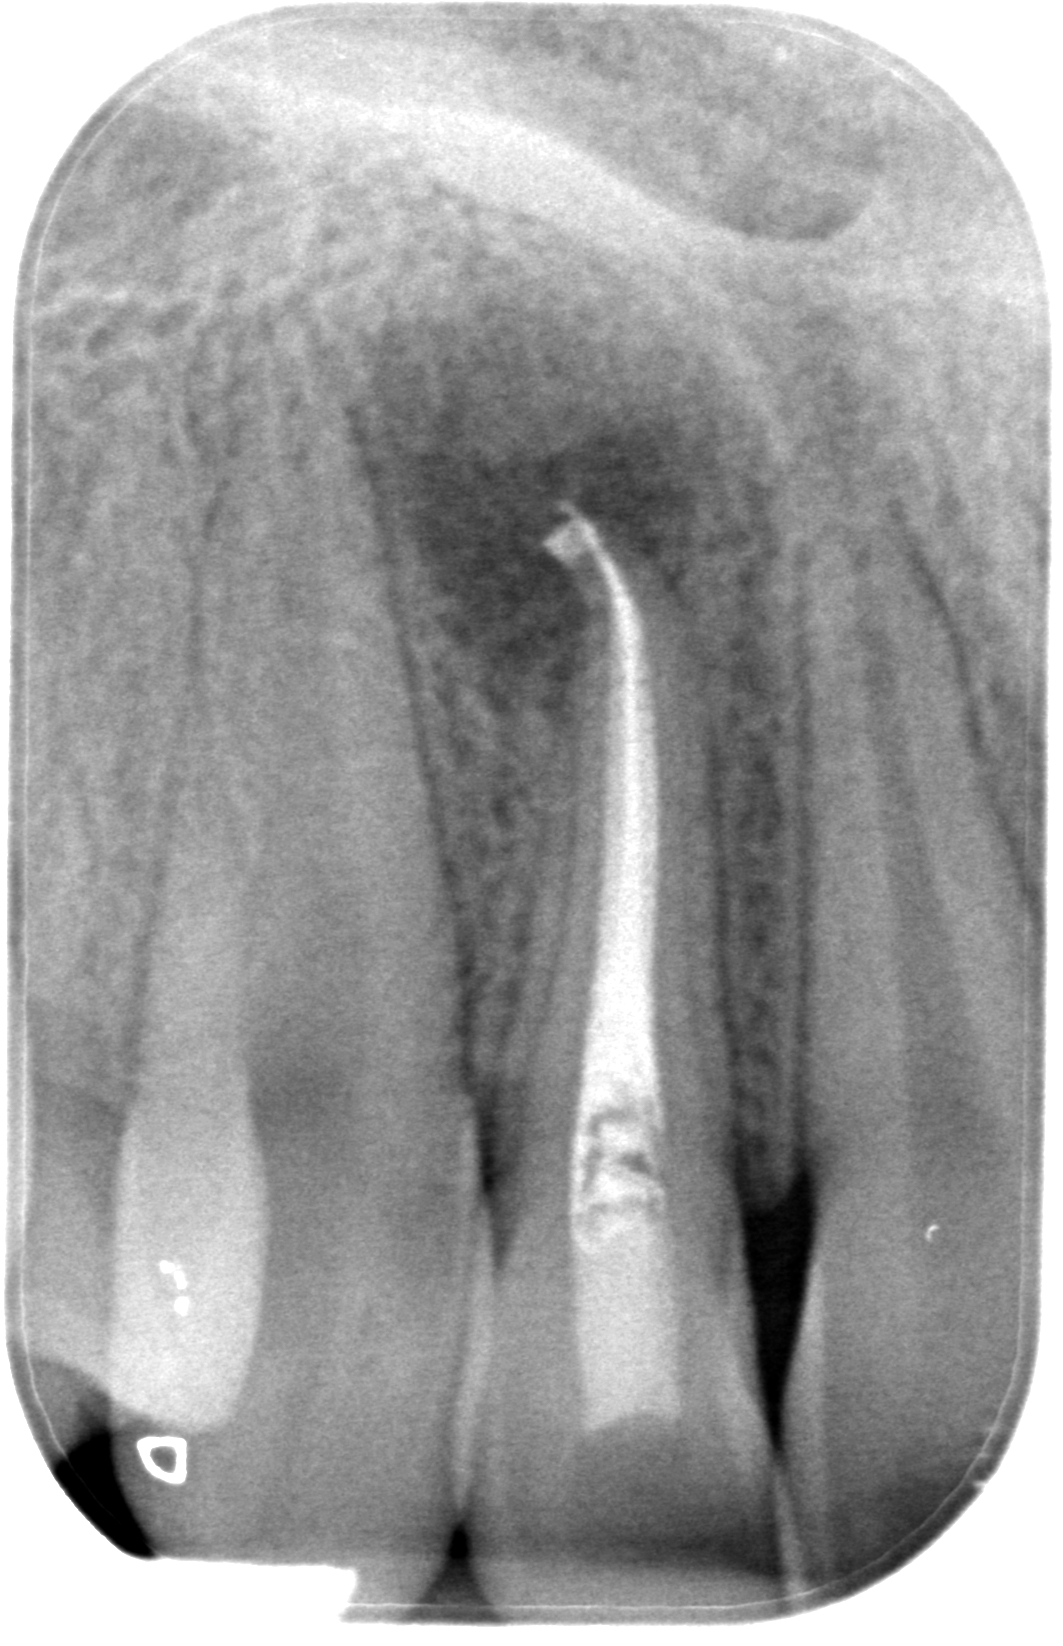

29.04.2019 Patientin LB, geb. am 07.05.2003, Zahn 12, WF-Kontrolle 32 Monate post WF